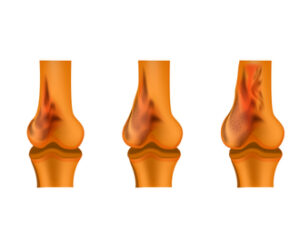

زراعة مفصل الركبة في الاردن ما هي زراعة مفصل الركبة عملية استبدال المفصل التالف بمفصل صناعي حديث. اسباب العملية خشونة الركبة الاصابات الشديدة التقدم في

افضل طرق علاج خشونة الركبة في عمان بدون جراحة | استشاري عظام ومفاصل افضل طرق علاج خشونة الركبة في عمان بدون جراحة خشونة الركبة تعتبر